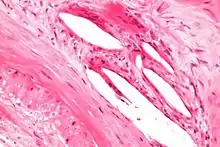

The internal elastic lamina or internal elastic lamella is a layer of elastic tissue that forms the outermost part of the tunica intima of blood vessels. It separates tunica intima from tunica media.

It is readily visualized with light microscopy in sections of muscular arteries, where it is thick and prominent, and arterioles, where it is slightly less prominent and often incomplete.[1] It is very thin in veins and venules.[1] In elastic arteries such as the aorta, which have very regular elastic laminae between layers of smooth muscle cells in their tunica media, the internal elastic lamina is approximately the same thickness as the other elastic laminae that are normally present.[2]

There is small amount of subendothelial connective tissue between basement membrane of endothelial cells and internal elastic lamina.[3]

Reduplication of internal elastic lamina can be seen in elderly individuals due to intimal fibroplasia, which is part of the aging process.[4]